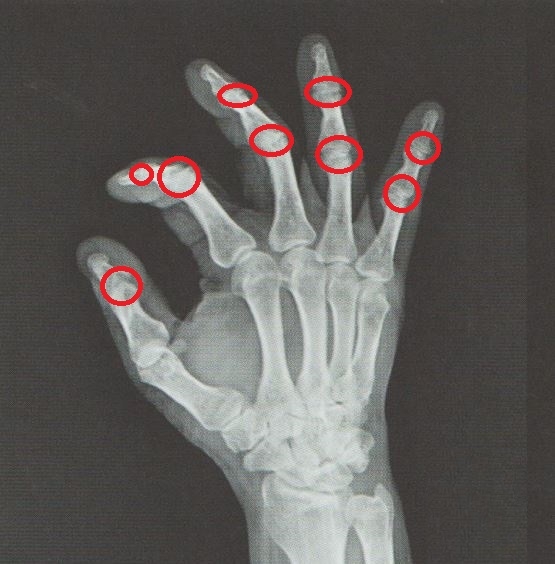

영상 검사에서는 PIP(근위지절) 및 DIP(원위지절) 관절 간격이 좁아지거나 골극이 형성되는 모습이 확인되는 경우가 있으며, 이는 전형적인 진행 양상으로 볼 수 있습니다.

▶ 주로 근위지절(PIP) 또는 원위지절(DIP) 관절에서 불편감 발생